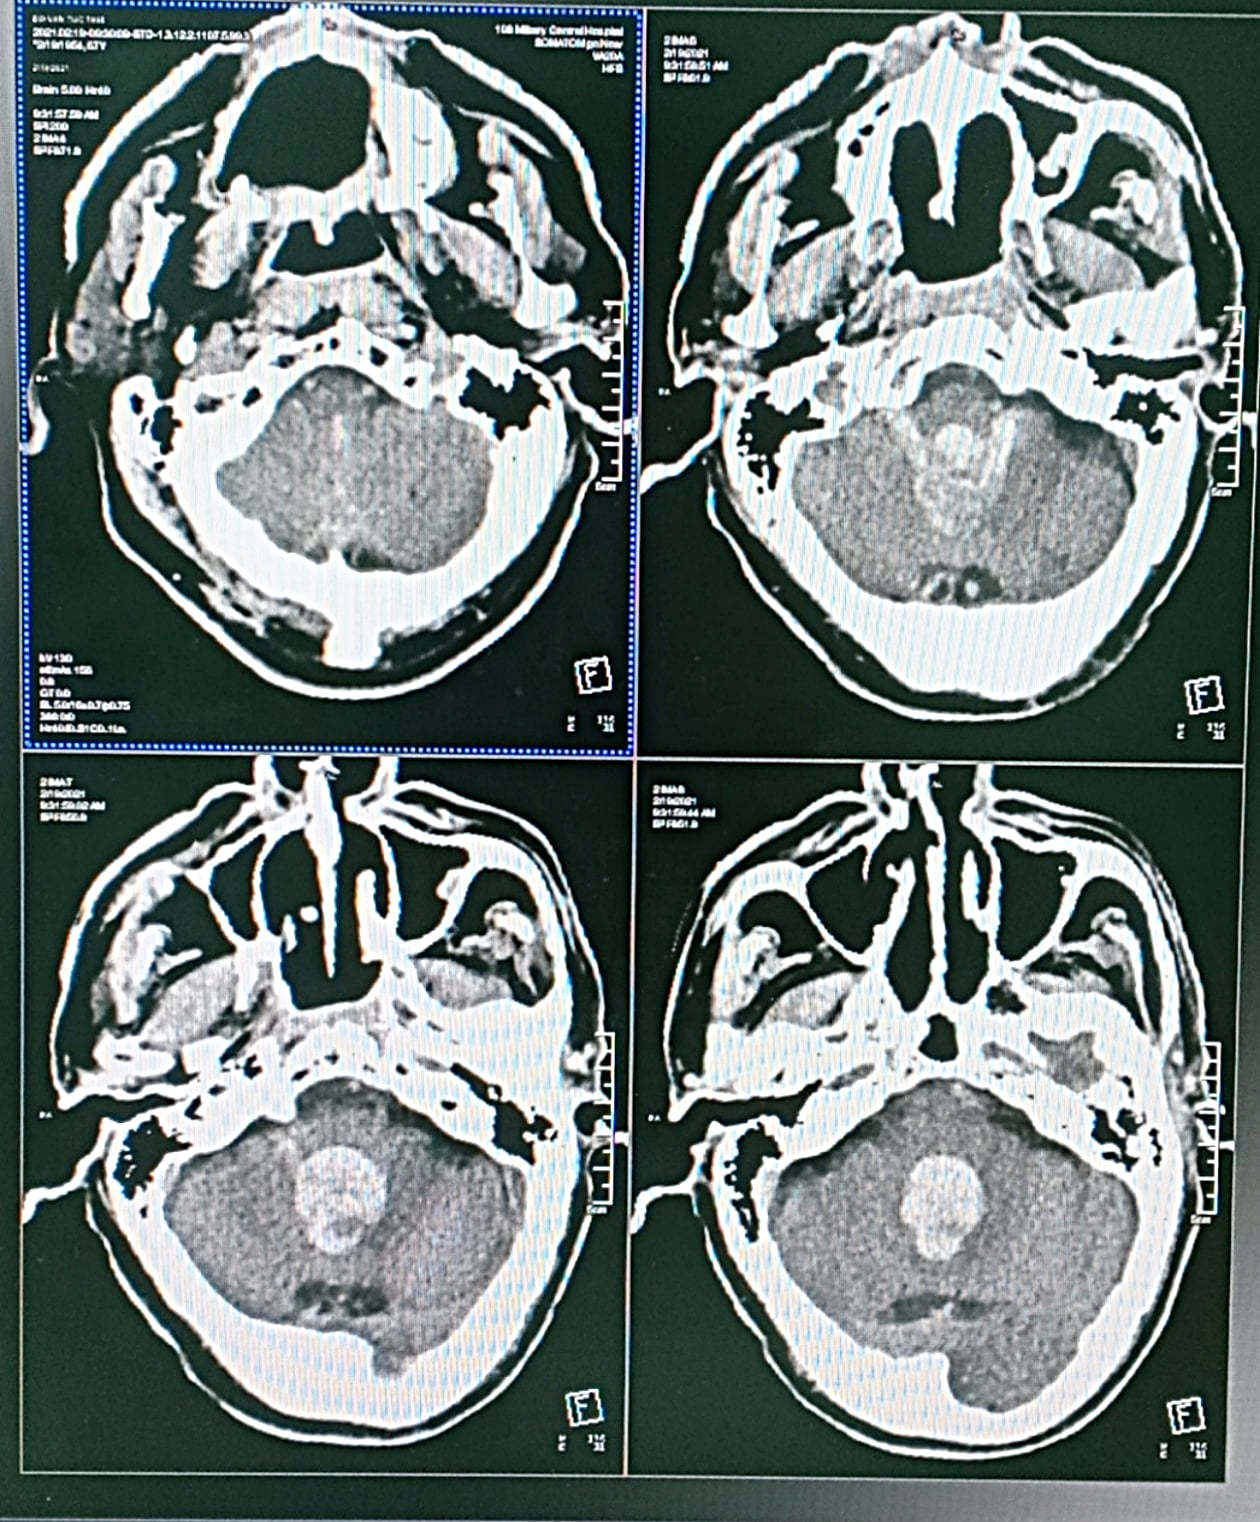

15/03/2021 18:23Người đàn ông Hà Nội đột quỵ, máu trong não đóng thành khuôn

Người đàn ông 67 tuổi ở Hà Nội thấy trong người hơi mệt, muốn đi nghỉ và dặn con cháu gọi dậy khi tới bữa cơm tối. Hai tiếng sau, khi người nhà gọi dậy, ông đã bất tỉnh.

Bệnh nhân được tuyến dưới chẩn đoán đột quỵ, chuyển đến Bệnh viện Trung ương Quân đội 108 trong tình trạng hôn mê sâu, gọi hỏi không đáp ứng, thở máy, tiên lượng đe doạ tử vong.

Tại Trung tâm Đột quỵ, bệnh nhân được điều trị bằng kỹ thuật dẫn lưu não thất mở kết hợp bơm thuốc tiêu sợi huyết. Đây là kỹ thuật mới được bệnh viện triển khai vài năm nay.

Bác sĩ Nguyễn Thị Loan, Trung tâm Đột quỵ cho biết, trước đây những người bệnh chảy máu não thất lớn gây lụt hệ thống não thất như trường hợp này sẽ có tỷ lệ tử vong là 100%, do máu chảy vào trong não thất đóng bánh lại thành khuôn không thể dẫn lưu ra ngoài.

Với kỹ thuật mới, thuốc tiêu huyết khối được tiêm qua dẫn lưu vào não thất, làm tan khối máu đông. Máu sau đó sẽ theo dẫn lưu chảy ra ngoài, giúp tăng cơ hội cứu sống nhiều người bệnh chảy máu não thất nặng.

Sau 3 tuần điều trị, hiện bệnh nhân đã tỉnh táo, tiếp xúc tốt, tự thở tốt, không liệt chân, tay, bước vào giai đoạn tập hồi phục chức năng.

Bác sĩ Loan đánh giá, tiên lượng điều trị của bệnh nhân này khá tốt, tỷ lệ phục hồi cao, tự đi lại được và trở về cuộc sống gần như bình thường sau tập luyện.